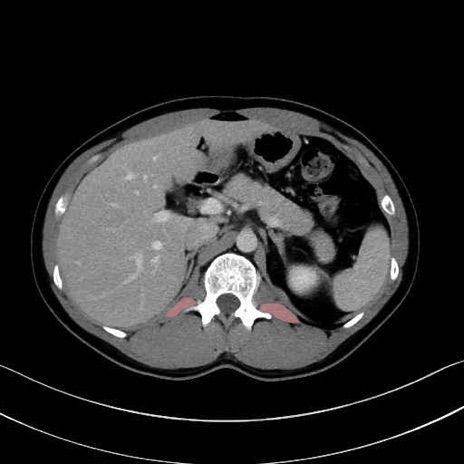

腰方形筋(quadratus lumborum muscle)のCT画像の解剖

1. 体幹部(腹部・背部・後腹壁)の筋肉

腰方形筋 (Quadratus lumborum)

広背筋 (Latissimus dorsi)

脊柱起立筋 (Erector spinae)

多裂筋 (Multifidus)